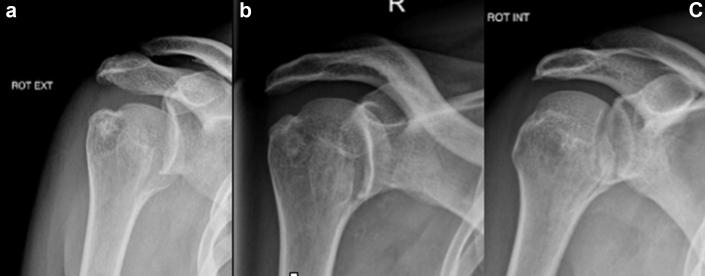

The utilization of computer planning and 3D-printed guide in the surgical management of a reverse Hill-Sachs lesion.

JSES Int. 2020 May 26;4(3):569-573. doi: 10.1016/j.jseint.2020.04.013. eCollection 2020 Sep.